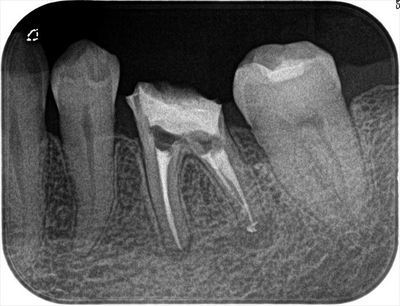

4根管の根管充填を終えた状態でのデンタルX線写真です。